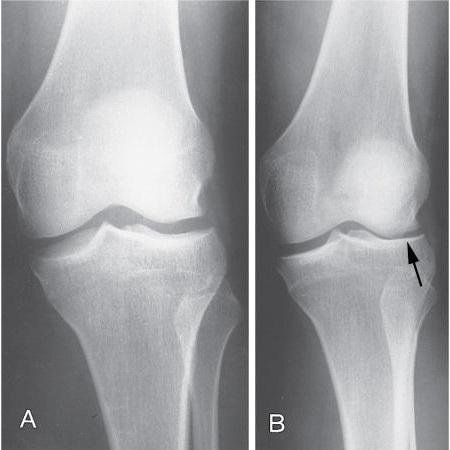

Діагностика хвороби Шляттера зазвичай не становить труднощів. Здоров’я коліна вивчається через фізичний огляд, включаючи пальпацію та рухи, які можуть викликати біль. Для уточнення можуть застосовувати рентген або ультразвукове дослідження, щоб виключити інші захворювання.